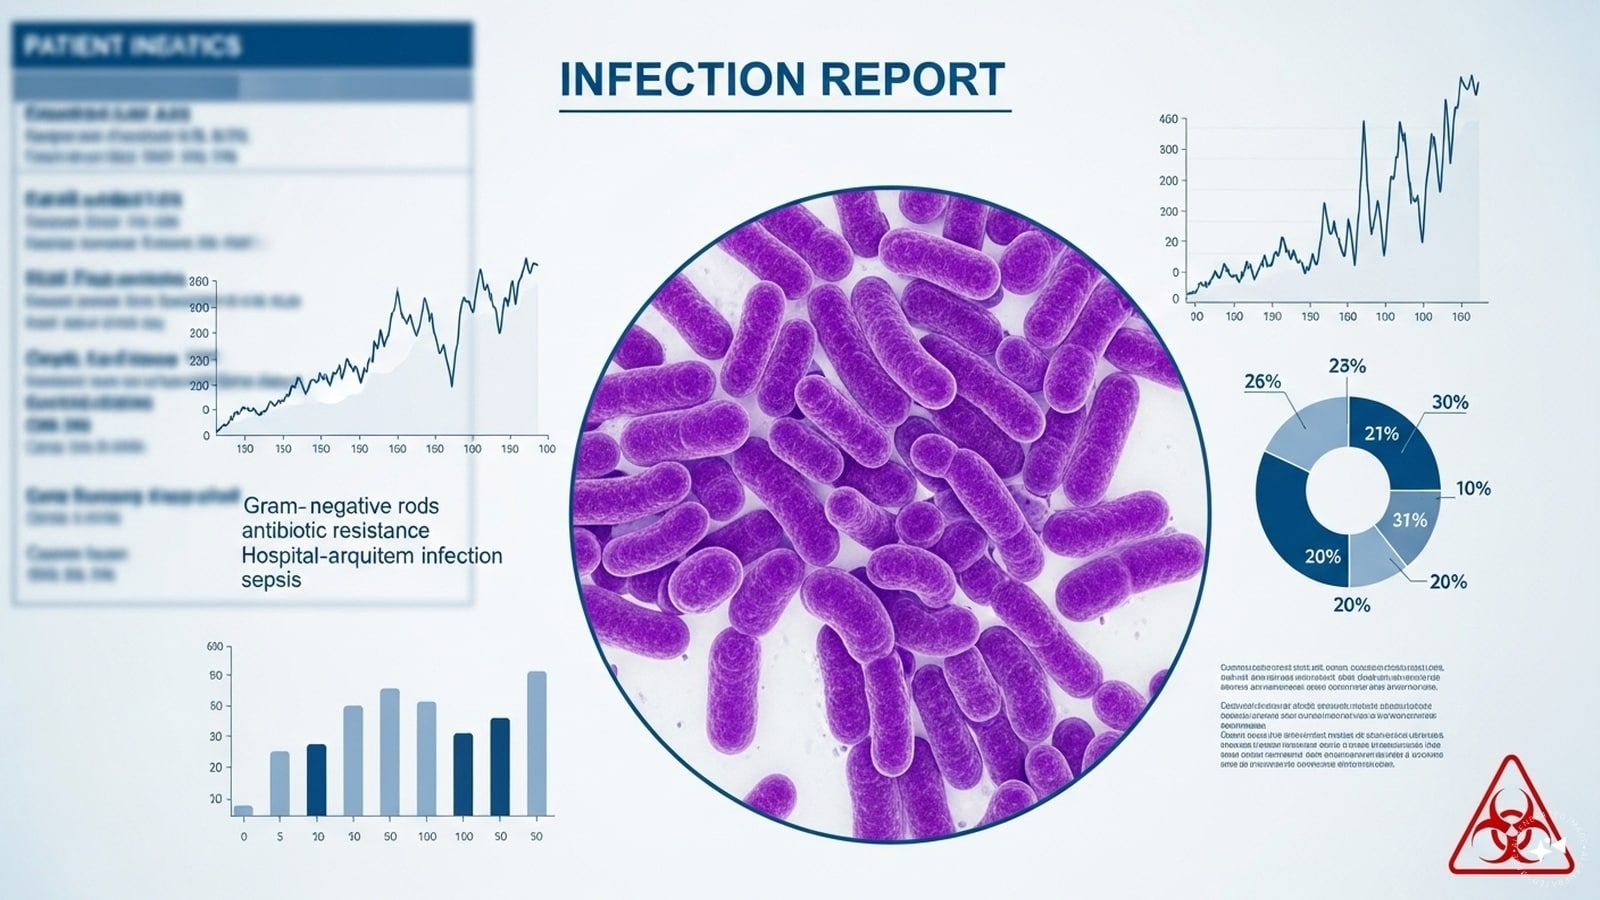

Frequent Infections: Weakened immunity from protein loss leaves the body prone to UTIs and respiratory infections that take longer to heal.

Chronic kidney disease affects 10% of the global population. If you notice these signs, consult a doctor early.